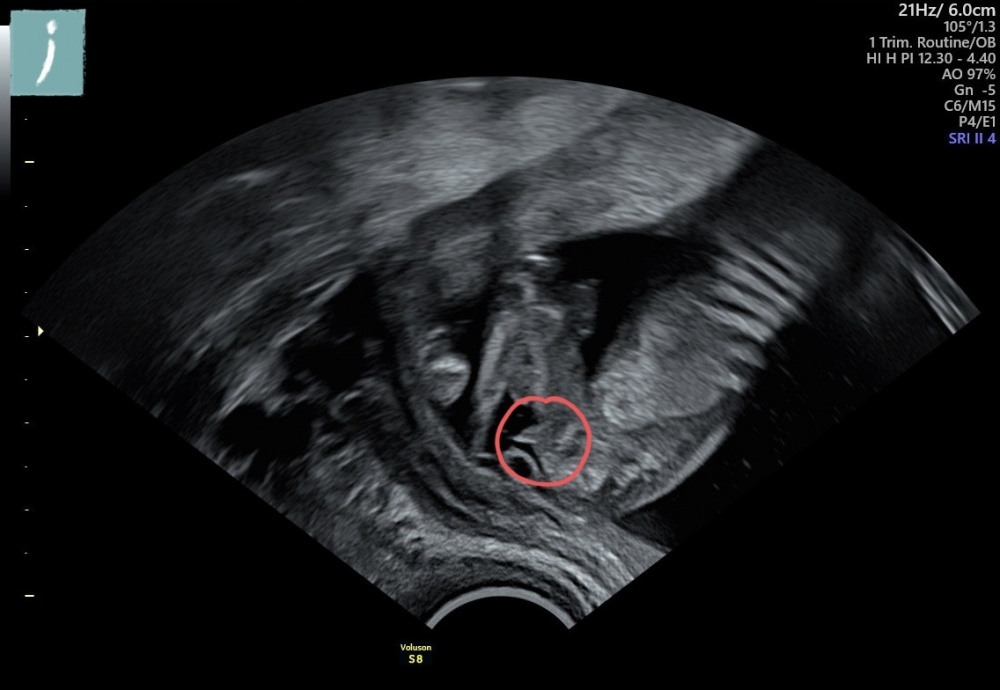

Die Ärztin beim CT meinte, dass wir sehr wahrscheinlich einen Buben bekommen. Ich bin gespannt, was meine Gyn im Juli sagt, oder ob es sich doch noch mal ändert. Was sagt ihr? Seht ihr auch einen Jungen?